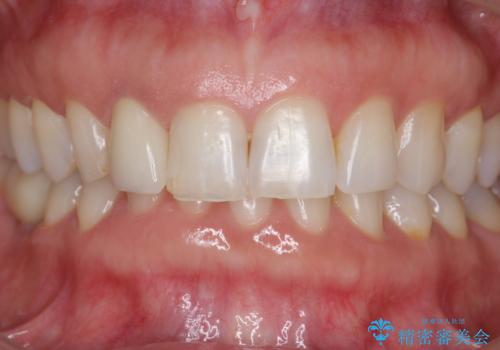

前歯の違和感 失活歯の根管治療とセラミック治療

- 前歯の付近、歯ぐきを押すと違和感を感じその改善を求めて来院されました。

X線検査の結果、失活(感染根管)であることが判明したので、感染根管治療後セラミック補綴を計画します。